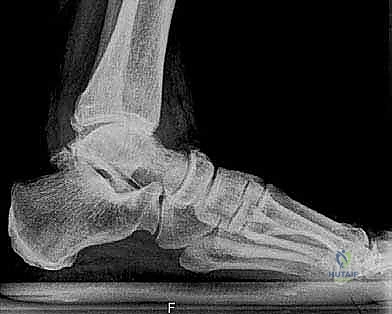

1. التقييم والتحضير قبل الجراحة

يتم إجراء فحوصات شاملة تشمل الأشعة السينية (X-rays)، والأشعة المقطعية (CT scan) لإنشاء نموذج ثلاثي الأبعاد لكاحل المريض. يساعد هذا د. هطيف في اختيار الحجم الدقيق للمفصل الصناعي وتحديد زوايا القطع بدقة متناهية.